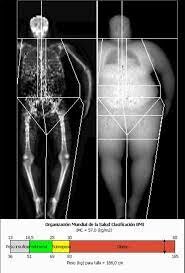

• Índice de Quetelet

Índice de Quetelet

L. A. J. Quetelet observó por primera vez que entre los adultos, el peso parecía aumentar en proporción al cuadrado de la estatura y estableció el índice de Quetelet, al que tiempo después en 1972 A. Keys y otros colegas le proporcionaron el nuevo nombre de Índice de Masa Corporal.